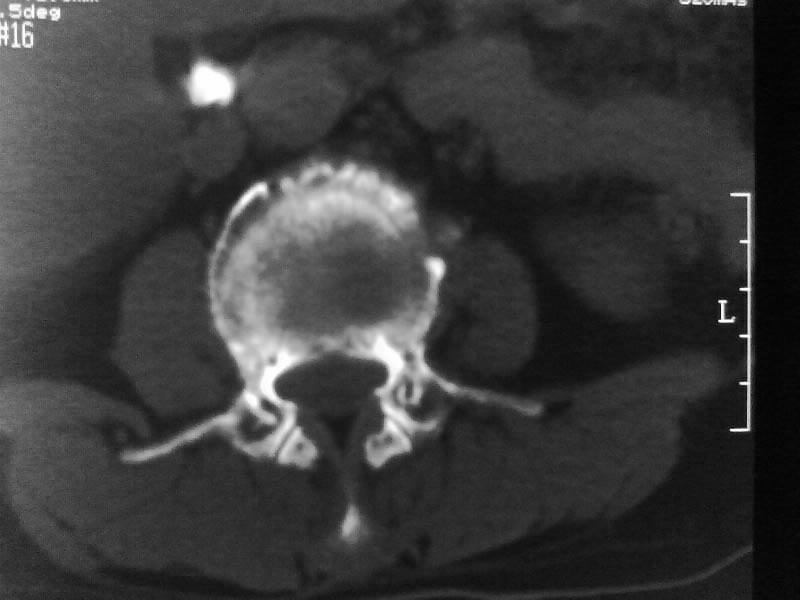

定位相示l2呈楔形改变(ct示陈旧性骨折改变,图像未传),l4.5椎体融合,以下是l4.5ct平扫.请各位看看,

考虑结核(有破坏、硬化及死骨)。

1、三四椎体结核,2、水平骶椎。

1、l1压缩性骨折(陈旧性)。

2、l3、4椎体结核。

就是腰1压缩性骨折,腰3\\4椎体结核(融合),水平骶椎.

支持 l1椎体陈旧性压缩性骨折;l3、4椎体结核(融合);水平骶椎。